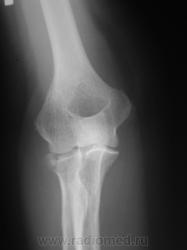

Травма. Пациент направлен на рентгенографию локтевого сустава.

перелом головки луча, встречается не так и часто.

Внутрисуставной,краевой перелом головки лучевой кости.